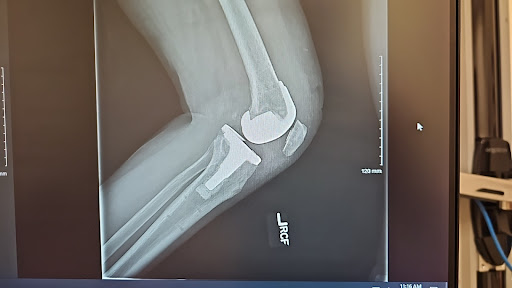

Had robotic total knee reolacemet surgery on my right knee in October and then had my left knee replaced in May. ...read moreread lessBarbara Margolies6/02/2024Excellent Doctor Had robotic total knee reolacemet surgery on my right knee in October and then had my left knee replaced in May. All together I feel 100% better. I am thrilled with the speed of the recovery. My incision looks fantastic, but more importantly, my knee feels amazing. I hardly and anybsututes removes and the skin gkuenqas very comforting. Thank you for doing an amazing job!read moreread lessBarbara Margolies5/21/2024 - I had a painful biceps and arthritis of my shoulder. Dr. Gendy did a right shoulder arthroscopic repair and clean out. My shoulder feels so much better already. I’m 3 months post surgery, done with PT, and back in the gym working out. I’m thrilled with recovery especially at the age of 77.read moreread lessCharlie Leger5/16/2024Outpatient Anterior Total Hip Replacement